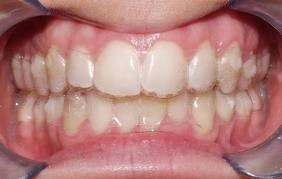

Jakmile je léčbou dosaženo patřičného výsledku, zuby jsou rovné a správně do sebe zakusují, dochází k sejmutí fixního aparátu. Následuje retenční fáze léčby.

Retenční fáze léčby

Každá ortodontická vada má přirozenou tendenci vracet se do původní pozice, tedy recidivovat. K zabránění recidiv je nutno nosit po léčbě sundávací rovnátko (retenční deska nebo fóliová dlaha) k udržení stavu vyrovnaných zubů. Tato retenční zařízení se nosí první měsíce po sejmutí fixního aparátu intenzivně (16 hodin denně), poté intenzita nošení postupně klesá. Zároveň po léčbě podlepujeme přední zuby ze zadní strany tenkým drátkem ( fixní retainer), který má také za úkol zuby po léčbě udržet v požadované pozici.